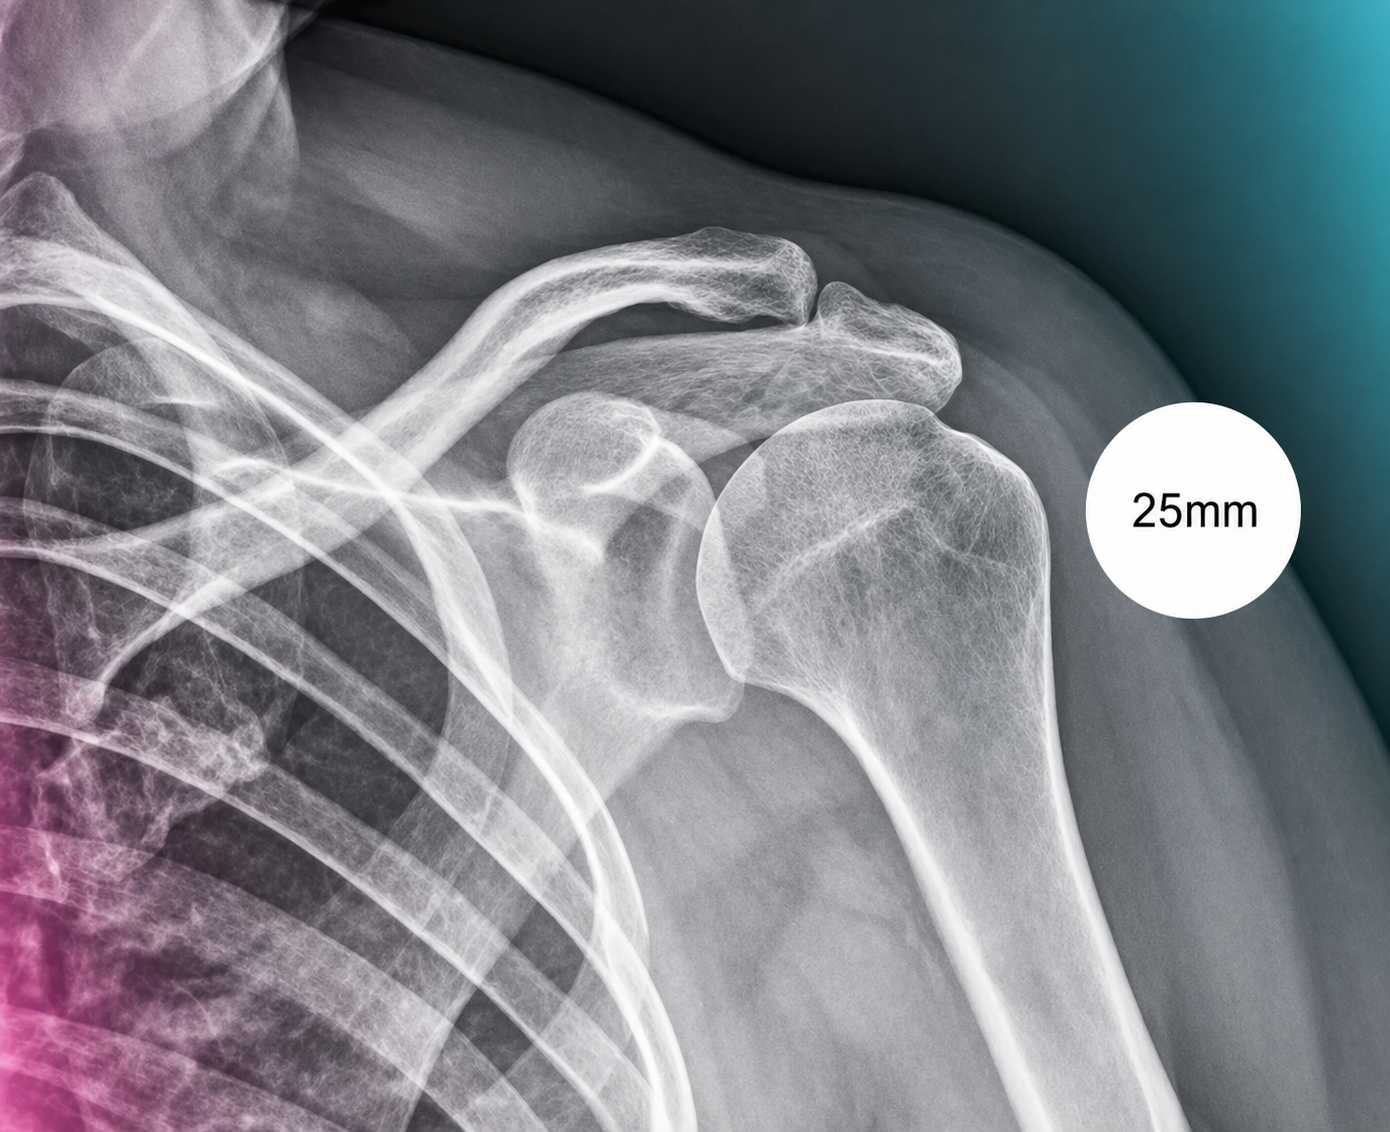

A compact guide for radiology teams on correct calibration sphere placement in orthopedic X-ray imaging. The marker must be positioned in the anatomical plane of the target joint so that digital scaling, measurements and preoperative templating remain clinically reliable.